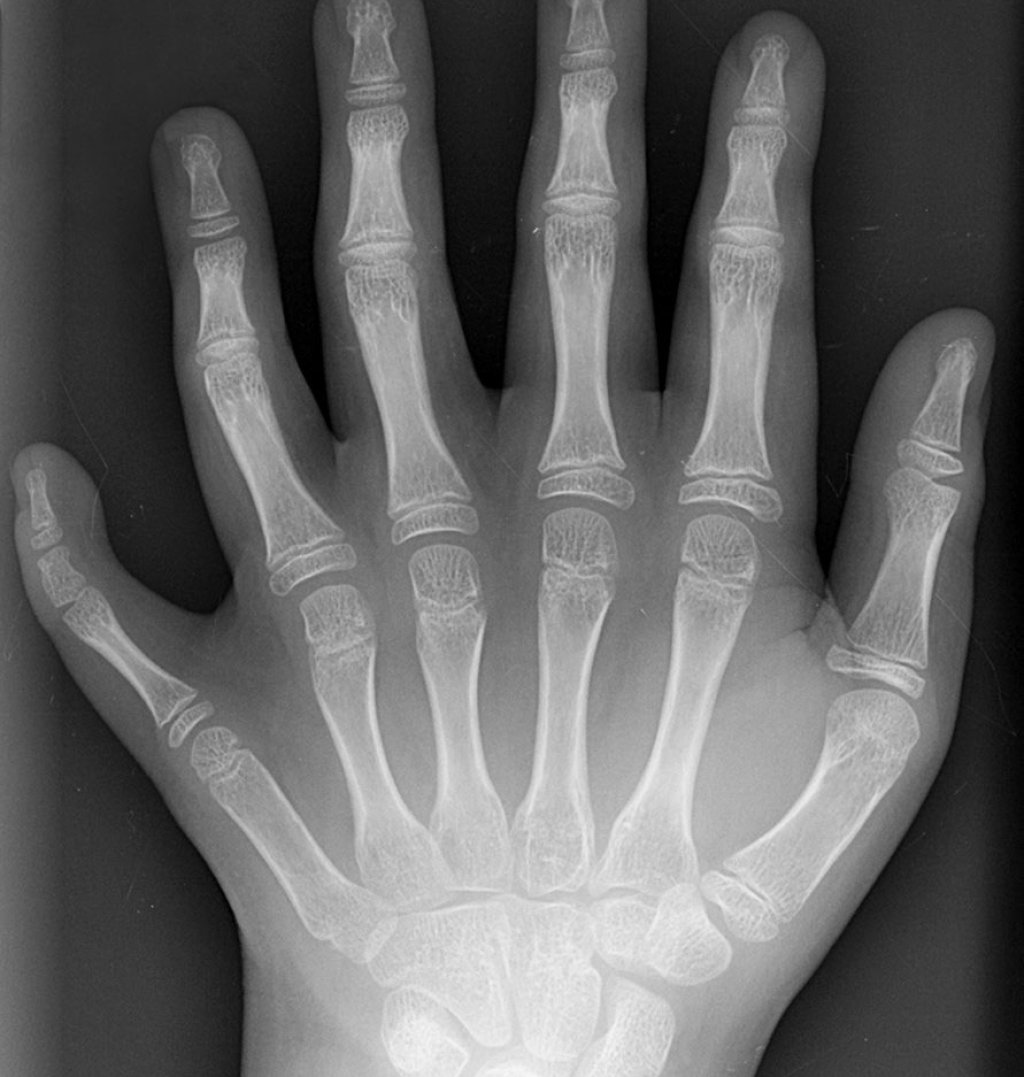

Polydactyly_01_Lhand_AP

Снимка: en:User:Drgnu23, subsequently altered by en:user:Grendelkhan, en:user: Raul654, and en:user:Solipsist., CC BY-SA 3.0 , via Wikimedia Commons